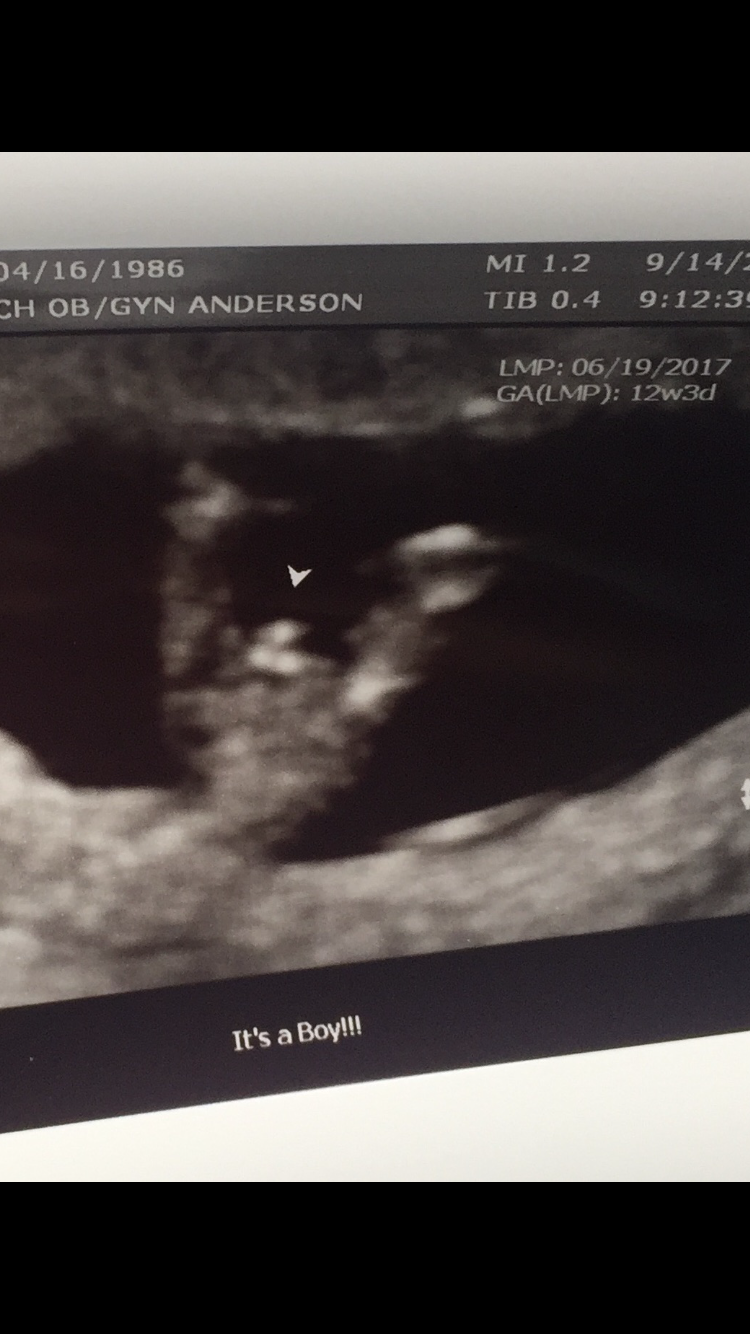

Yes. I had NIPT testing done (chromosomal tests through a blood draw) which said boy. When I went in for my 12 week scan, I already knew he was a boy because of the NIPT results but the ultrasound tech showed me his little peepee clear as day. This is my 12 week US.